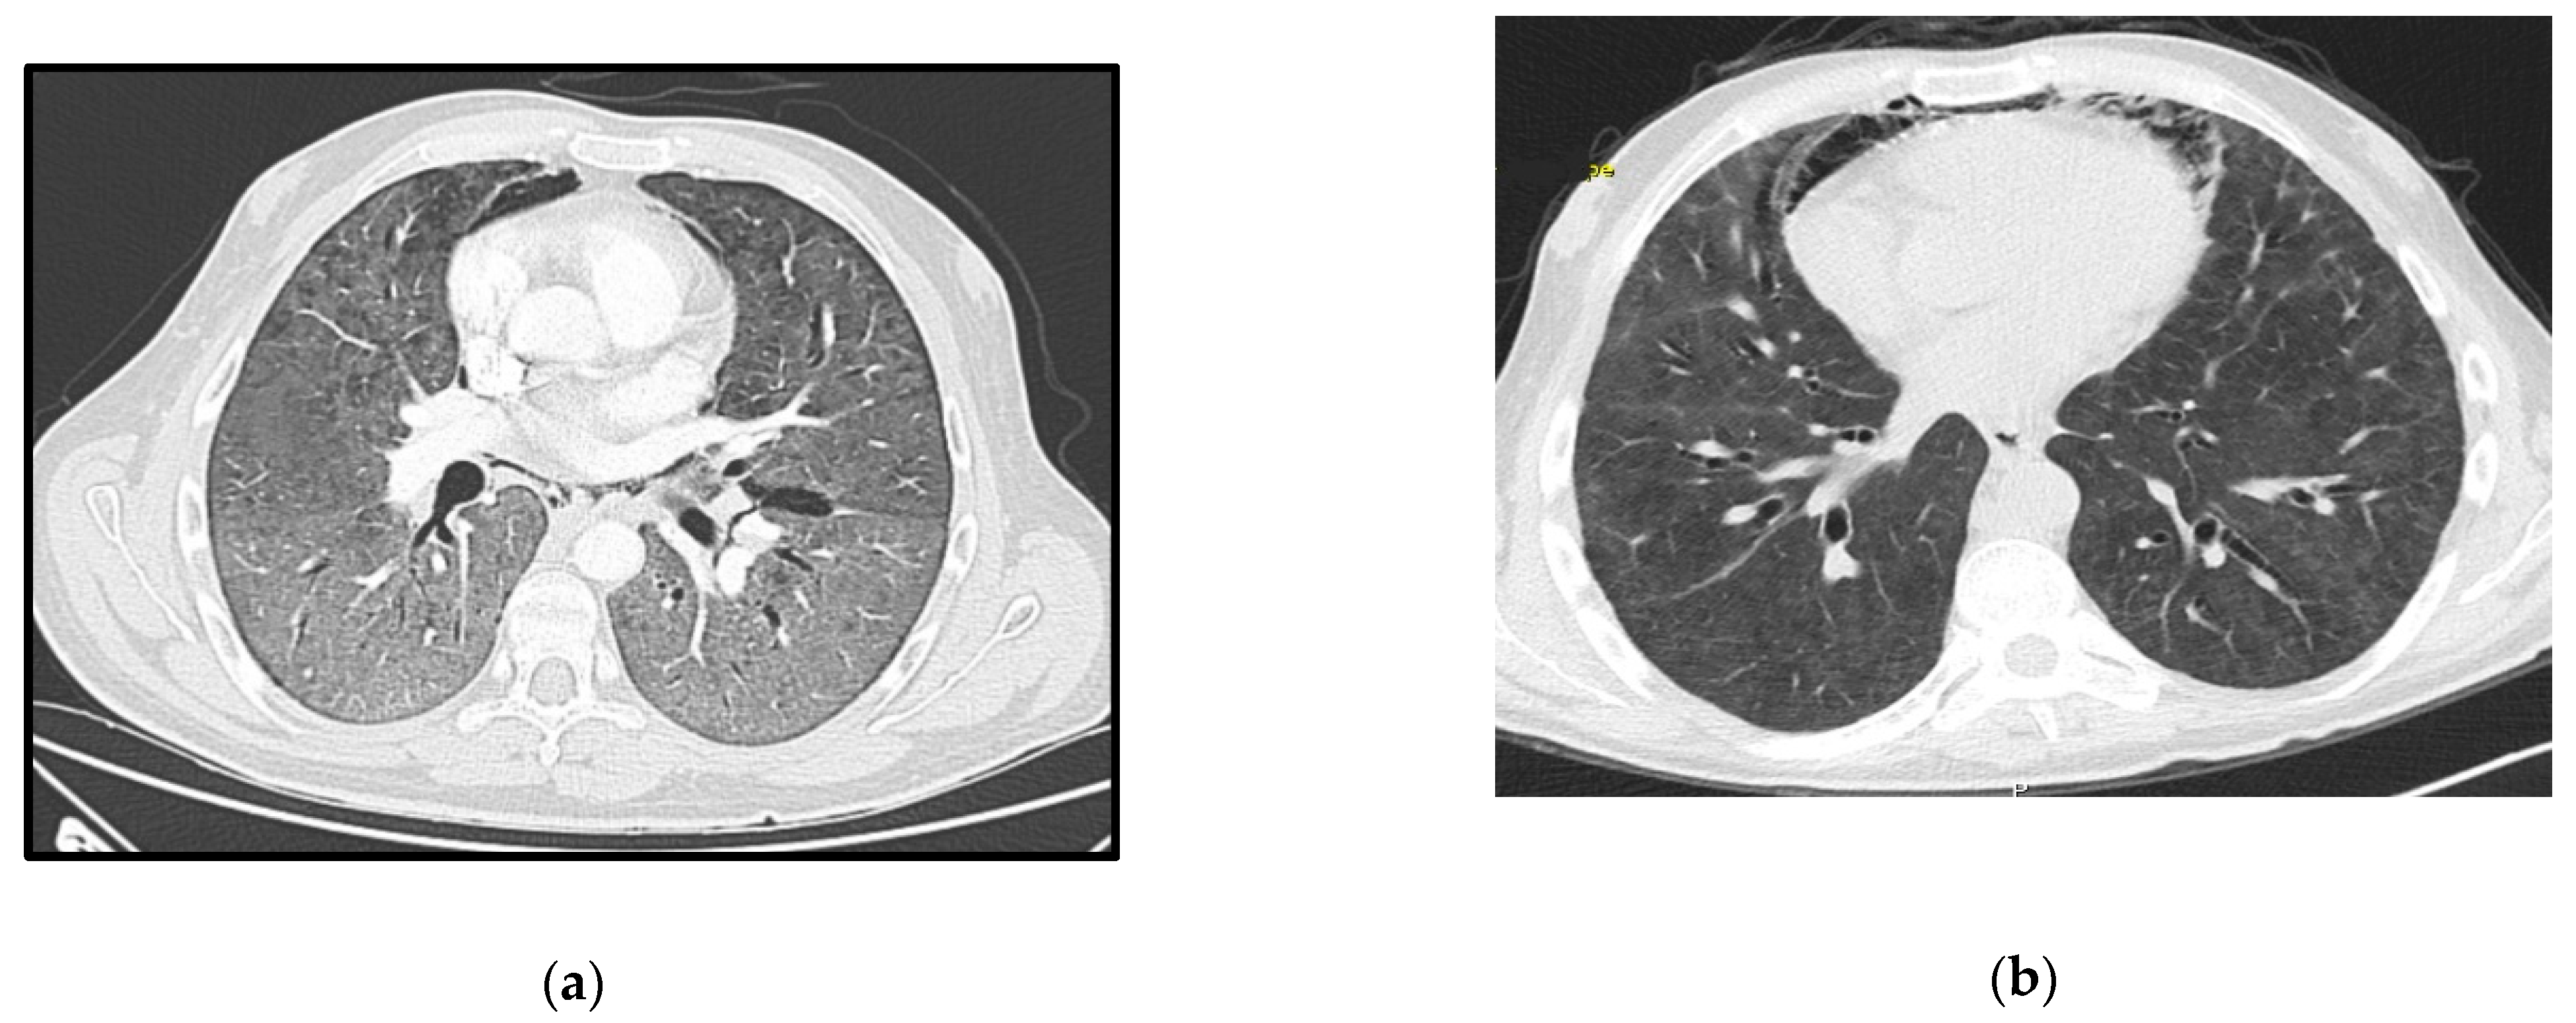

The patient presented at the ER with a 3-week history of worsening cough, dyspnea, and fever. Initial assessment showed hypoxia, fever (39 °C), elevated CRP, 6 CD4+ lymphocytes/mm3 and several ground glass opacities on thoracic CT-scan (Figure 4a). He started empirical treatment with TMP-SMX plus corticosteroids at the recommended PJP treatment dosage and was admitted to the ward. The need for oxygen support increased in the next few hours and the patient responded poorly to HFOT. Twenty-four hours later he was admitted to the ICU and VV-ECMO was started. No tracheal intubation was performed. PJP was confirmed by positive immunofluorescence in BAL.

He was transferred to the ward for rehabilitation after 37 days of ICU stay, and already on ART. The follow-up CT-scan can be seen in Figure 4b.

Figure 4. Case 4 thoracic CT-scan at diagnosis (a) and follow-up (b).